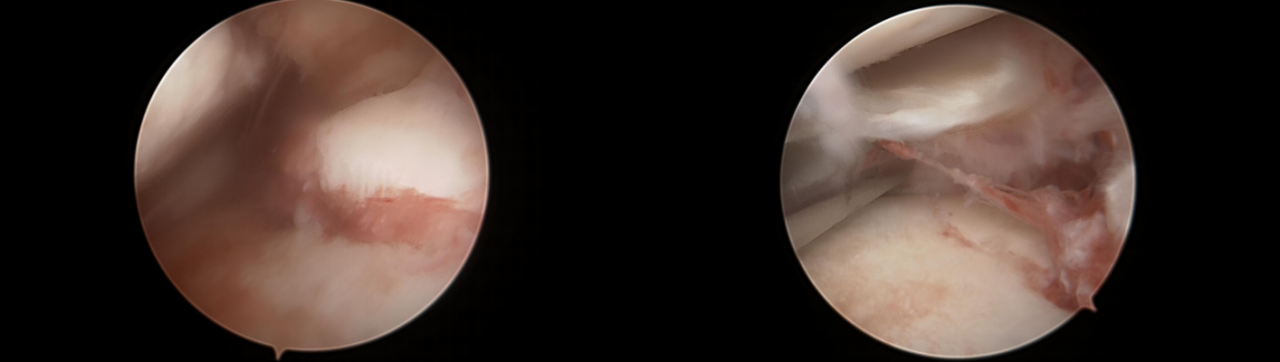

步骤1:暴露骨折段,插入定位器械,并构建一个直径为4.0mm的骨隧道。

步骤2:插入两条PDS线并引入高强线,分别并将其穿过后交叉韧带,以形成初始的吊带环。

第三步:双套环高强线复位骨折块,并穿入固定微孔钛板。

步骤4:将一根高强度缝合线穿过骨隧道,并牢牢收紧,以准确复位骨折段。

第五步:拉紧双环以稳定骨折部位,并抓住两条牵引缝线。

步骤6:紧固牵引缝线以防止固定环滑脱。